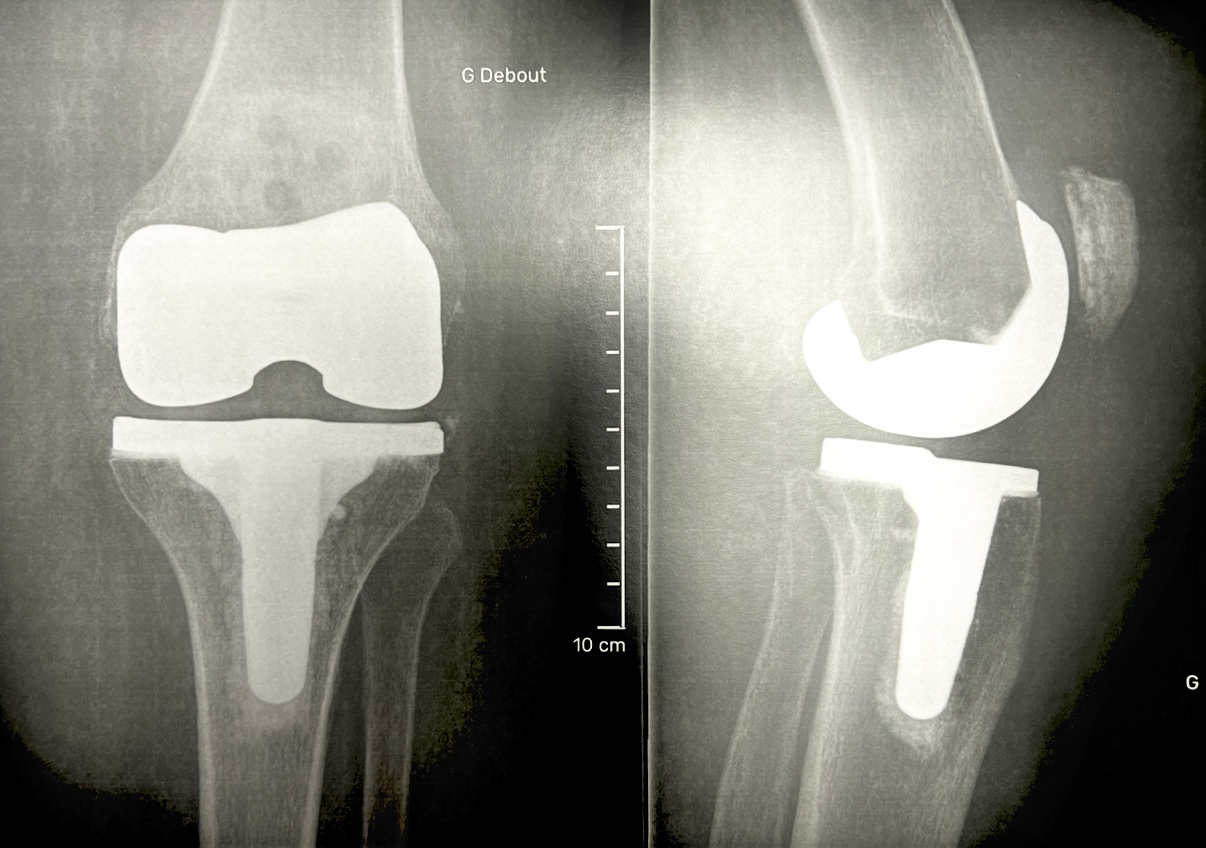

Prothèse totale du genou Entièrement créée sur Mesure

L’implantation d’une prothèse de genou consiste à remplacer les surfaces articulaires du genou (fémur, tibia, rotule) lorsqu’elles sont usées et détruites. Les causes de l'atteinte articulaire sont les plus souvent l'arthrose, et plus rarement un rhumatisme articulaire, une séquelle de fracture ou une séquelle de rupture ligamentaire… Lorsque la pathologie dégénérative de votre genou est trop évoluée il n’est plus possible de proposer un traitement conservateur à votre pathologie articulaire. L’implantation d’une Prothèse Totale de Genou (PTG) devient alors la solution ultime pour vous permettre de retrouver l’autonomie fonctionnelle que vous avez perdue et faire diminuer de façon remarquable ou disparaître vos douleurs articulaires.

Cette dernière prothèse est fabriquée sur mesure dans son intégralité selon votre anatomie osseuse et articulaire. Les guides de coupes osseuses adaptés à votre déformation seront spécifiquement fabriqués pour vous mais aussi la prothèse métallique définitive. Ainsi vous disposerez d'une prothèse unique spécialement créée pour vous. Cependant le choix de l’implantation de l’une ou l’autre type de prothèse revient à la décision de votre chirurgien qui analysera de façon globale votre anatomie osseuse, vos déformations articulaires et la cinématique du mouvement de votre genou. |

Puis la prothèse unique spécialement fabriquée pour vous sur mesure sera fixée dans l'os par impaction et scellée par du ciment chirurgical. A la fin de l'intervention, un drain est souvent mis en place permettant d'évacuer le saignement résiduel.